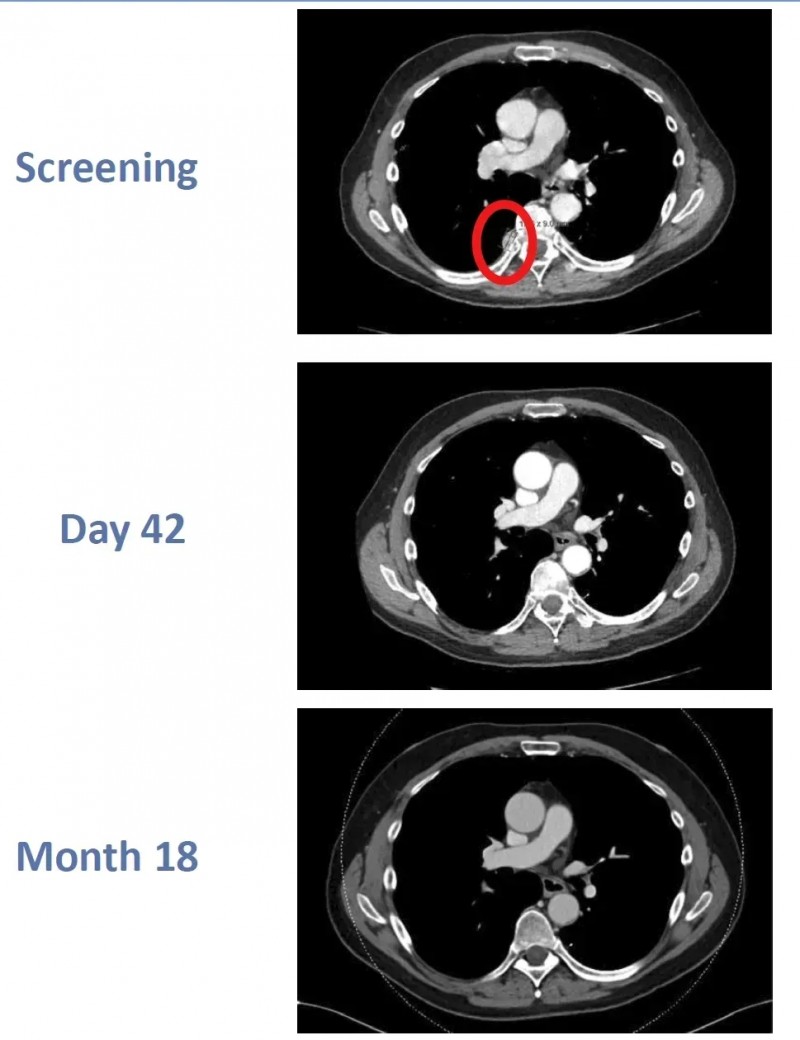

《Anticancer Research》曾报道一则经典案例:一位61岁男性患者确诊位右侧透明细胞型肾细胞癌(3级,pT1b期)伴肺转移,行根治性肾切除术后接受3个月干扰素α(IFN-α)治疗,CT显示肿瘤负荷无明显变化。

治疗转折出现在IFN-α洗脱期1个月后:患者通过白细胞分离术获取外周血单核细胞(PBMC),静脉注射IL-2与唑来膦酸,随后输注活化的Vγ2Vδ2T细胞。

疗效令人振奋:患者多发性肺转移灶在回输Vγ2Vδ2 T细胞3个疗程后显著缓解,6个疗程后完全消失;完成最后一个疗程后,患者持续2年保持完全缓解(CR)状态(详见下图),且未接受额外针对肾癌的治疗。

▲图源“anticancer research”,版权归原作者所有,如无意中侵犯了知识产权,请联系我们删除